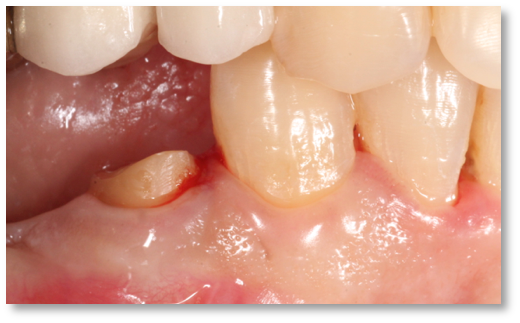

Before and after Periodontal Therapy

| Untreated severe gum disease | Gum disease treated and stabilised by Dr Halai |